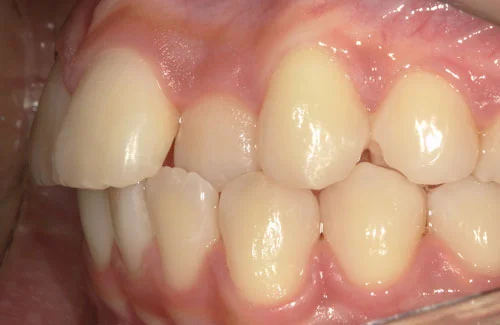

<症例7>歯がガタガタで噛み合わせが悪くお悩み

抜歯無し・マウスピースのみで矯正した症例です。

もともと歯列弓が非常に狭く、V字に近い形をしていたので噛み合わせも非常に不安定でした。

また、下顎前歯部がかなり上の方に生えていたため、下の前歯が上の前歯を突き上げてしまい出っ歯の状態になっていました。

現在では見た目はもちろん、臼歯の噛み合わせも改善しております。

奥歯の患者様も大喜びでした。

患者様と症状

主訴:歯のガタガタ、噛み合わせが悪い

性別・年齢:20代女性

問題点:叢生(重度)、V字歯列弓、ディープバイト

診断:前歯部の叢生を伴うアングルⅠ級、骨格性Ⅰ級の不正咬合

主なリスク:臼歯の移動に伴い一時的に咬合しにくくなる、歯肉退縮

症状:叢生(そうせい) 過蓋咬合(かがいこうごう)

治療内容

治療期間:1年10ヶ月

治療費用:990,000円(税込)

プラン:Full2プラン

抜歯:無し

再診治療費:無し

追加治療費:無し

保定装置費:無し

治療前後の写真